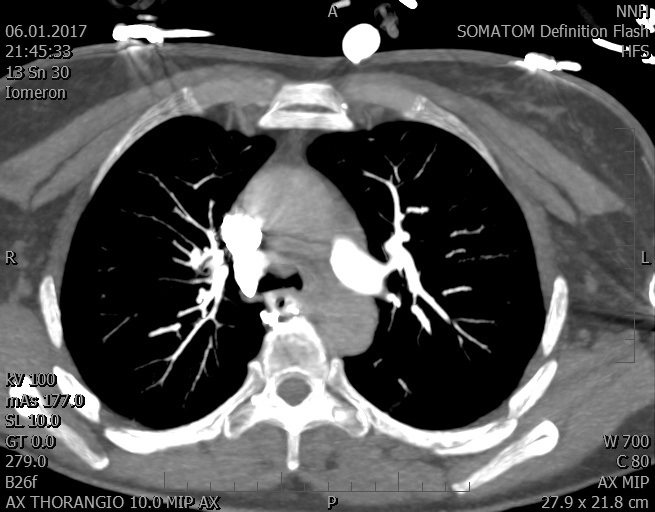

Video 1 - Akutní koronarografie prokázala normální nález na věnčitých tepnách s výjimkou suspekce na lehký spasmus na pravé koronární tepně.Echokardiograficky byla zjištěna těžká dysfunkce dilatované levé komory s nezvětšenou pravou komorou (video 2).

Video 2 - Echokardiograficky byla zjištěna těžká dysfunkce dilatační levé komory s nezvětšenou pravou komorou.Pro nejasnou příčinu zástavy jsme provedli i vyšetření výpočetní tomografií (CT), které vyloučilo plicní embolizaci (série 1 - soubory na konci článku). V den přijetí při přetrvávající oběhové nestabilitě byla nemocná opakovaně defibrilována pro fibrilaci komor se stabilizací rytmu po podání amiodaronu a mesocainu. Dle hemodynamických měření se jednalo o těžký kombinovaný šok. Vstupní laboratorní vyšetření bylo bez větších pozoruhodností. Posléze jsme doplnili anamnézu od příbuzných a zjistili, že pacientka užila do dvou hodin před srdeční zástavou první tabletu amoxicilinu na lehký respirační infekt. Při nevýtěžnosti vstupních vyšetření a nových anamnestických informacích jsme doplnili 14 hodin po kolapsu vyšetření koncentrace tryptázy v séru, která byla extrémně zvýšena (tabulka 2), což nás vedlo k podezření na anafylaxi.